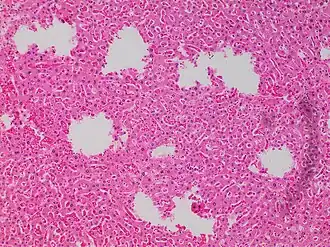

![Tearing artifacts, such as can be caused by: - Microtomy with a nick or blemish in the knife edge.[5] - Traction of the sections. - Too much or too little alcohol dehydration.[5] - Sectioning calcified parts, which can be decalcified or removed.[5]](./_assets_/Microscopy_of_liver_parenchyma_with_tearing_artifacts.jpg)

-

Formalin pigment artifacts -

Air bubble entrapment artifact in a shoulder joint biopsy -

Staining artifacts by residual wax, resulting in pale areas where cellular structures are not discernible -

A separation artifact in top image makes the tumor look incompletely excised, but the next microtomy level (bottom image) shows a surgical margin of connective tissue. -